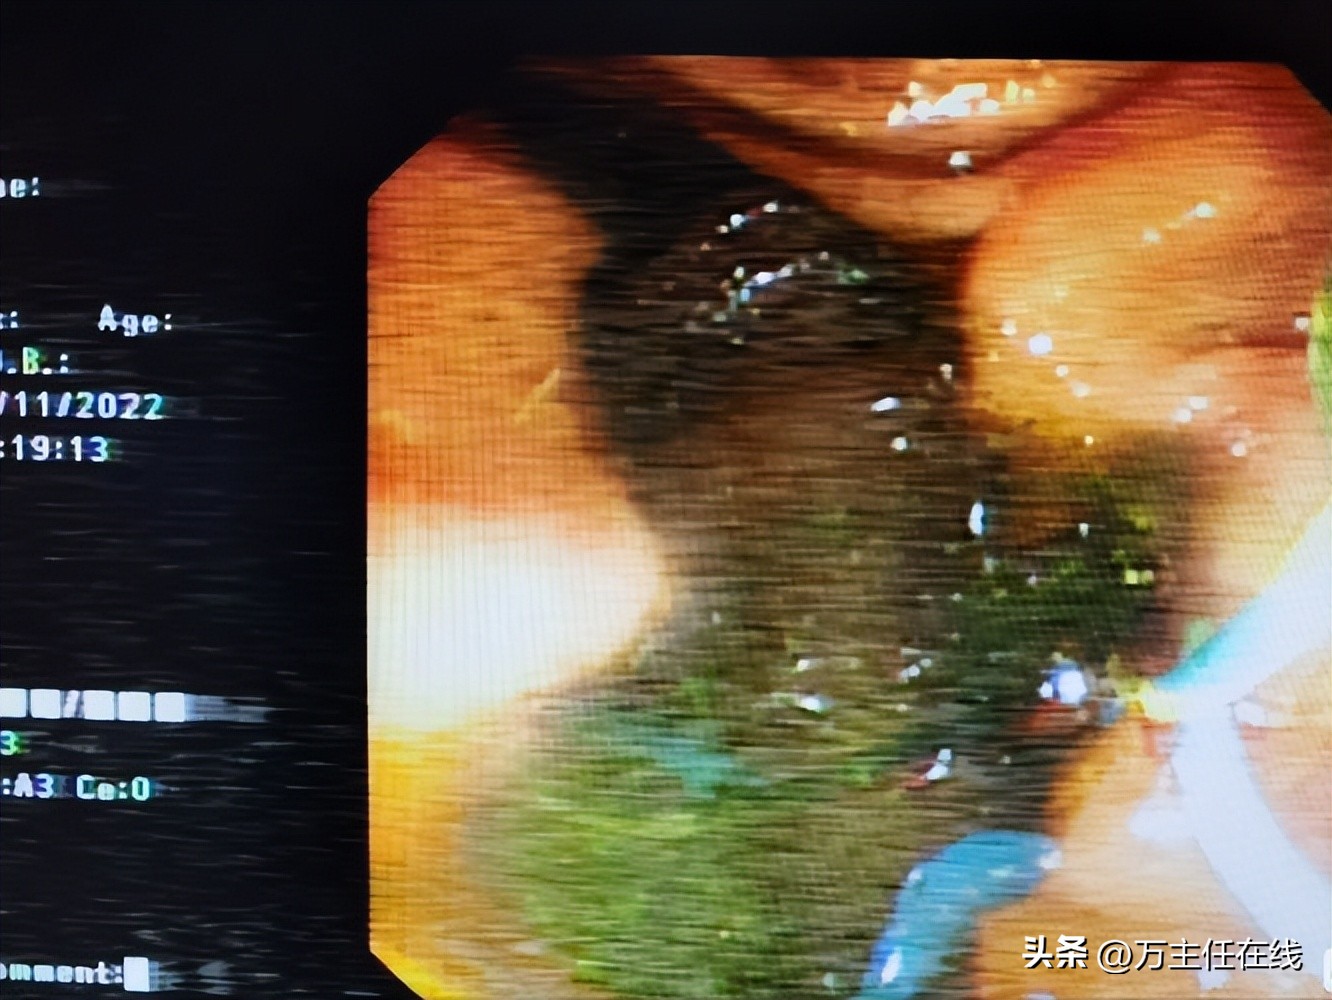

SpygIass探查胆管内泥沙样结石

Spyglass探查胆管内脓性胆汁,予冲洗引流